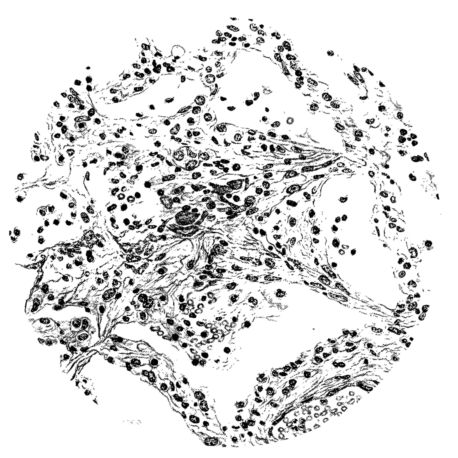

FIG. II. AUTOPSY NO. 98. DRAWING OF A SECTION THROUGH A TRACHEA SHOWING NECROTIZING HEMORRHAGIC INFLAMMATORY PROCESS OF THE MUCOSA.

The changes are less marked, perhaps, in the trachea than in its finer ramifications. The mucosa is constantly more or less destroyed and large areas, usually focal, are entirely devoid of their epithelial covering. This is replaced by a sparse exudate, composed largely of red blood cells, mucus, a small amount of fibrin, and nuclear fragments (Fig. II). It may dip into the submucosa for a short distance, but usually these indentures are associated with the ducts of the mucous glands into which the inflammatory reaction extends. A more striking feature than the exudate, however, is the edema and the congestion of the submucosa. The loose areolar tissue of the submucosa is spread widely apart, and throughout it distended blood vessels are very conspicuous. Occasionally such a vessel is broken and actual hemorrhage appears in the submucosa. Occasionally, too, the inflammation extends down the duct to the mucous gland itself, and here, also, aplastic inflammatory reaction is evident, inasmuch as the acini now stain intensely red with the cells undifferentiated from each other and specked here and there by broken remains of the dead nuclei (Fig. III). After the disease has continued for a short period, even at the end of five or six days, some regeneration of the epithelial lining may be seen (3) (Fig. IV). But despite this, the acute picture persists, and there goes on, side by side, an attempted repair characterized by epithelial regeneration and the same evidence of acute change. Since the lesion is essentially a superficial one, scars or contractures of any extent are not encountered in the trachea, even in examples of the disease that have ended fatally only after many weeks.[4]